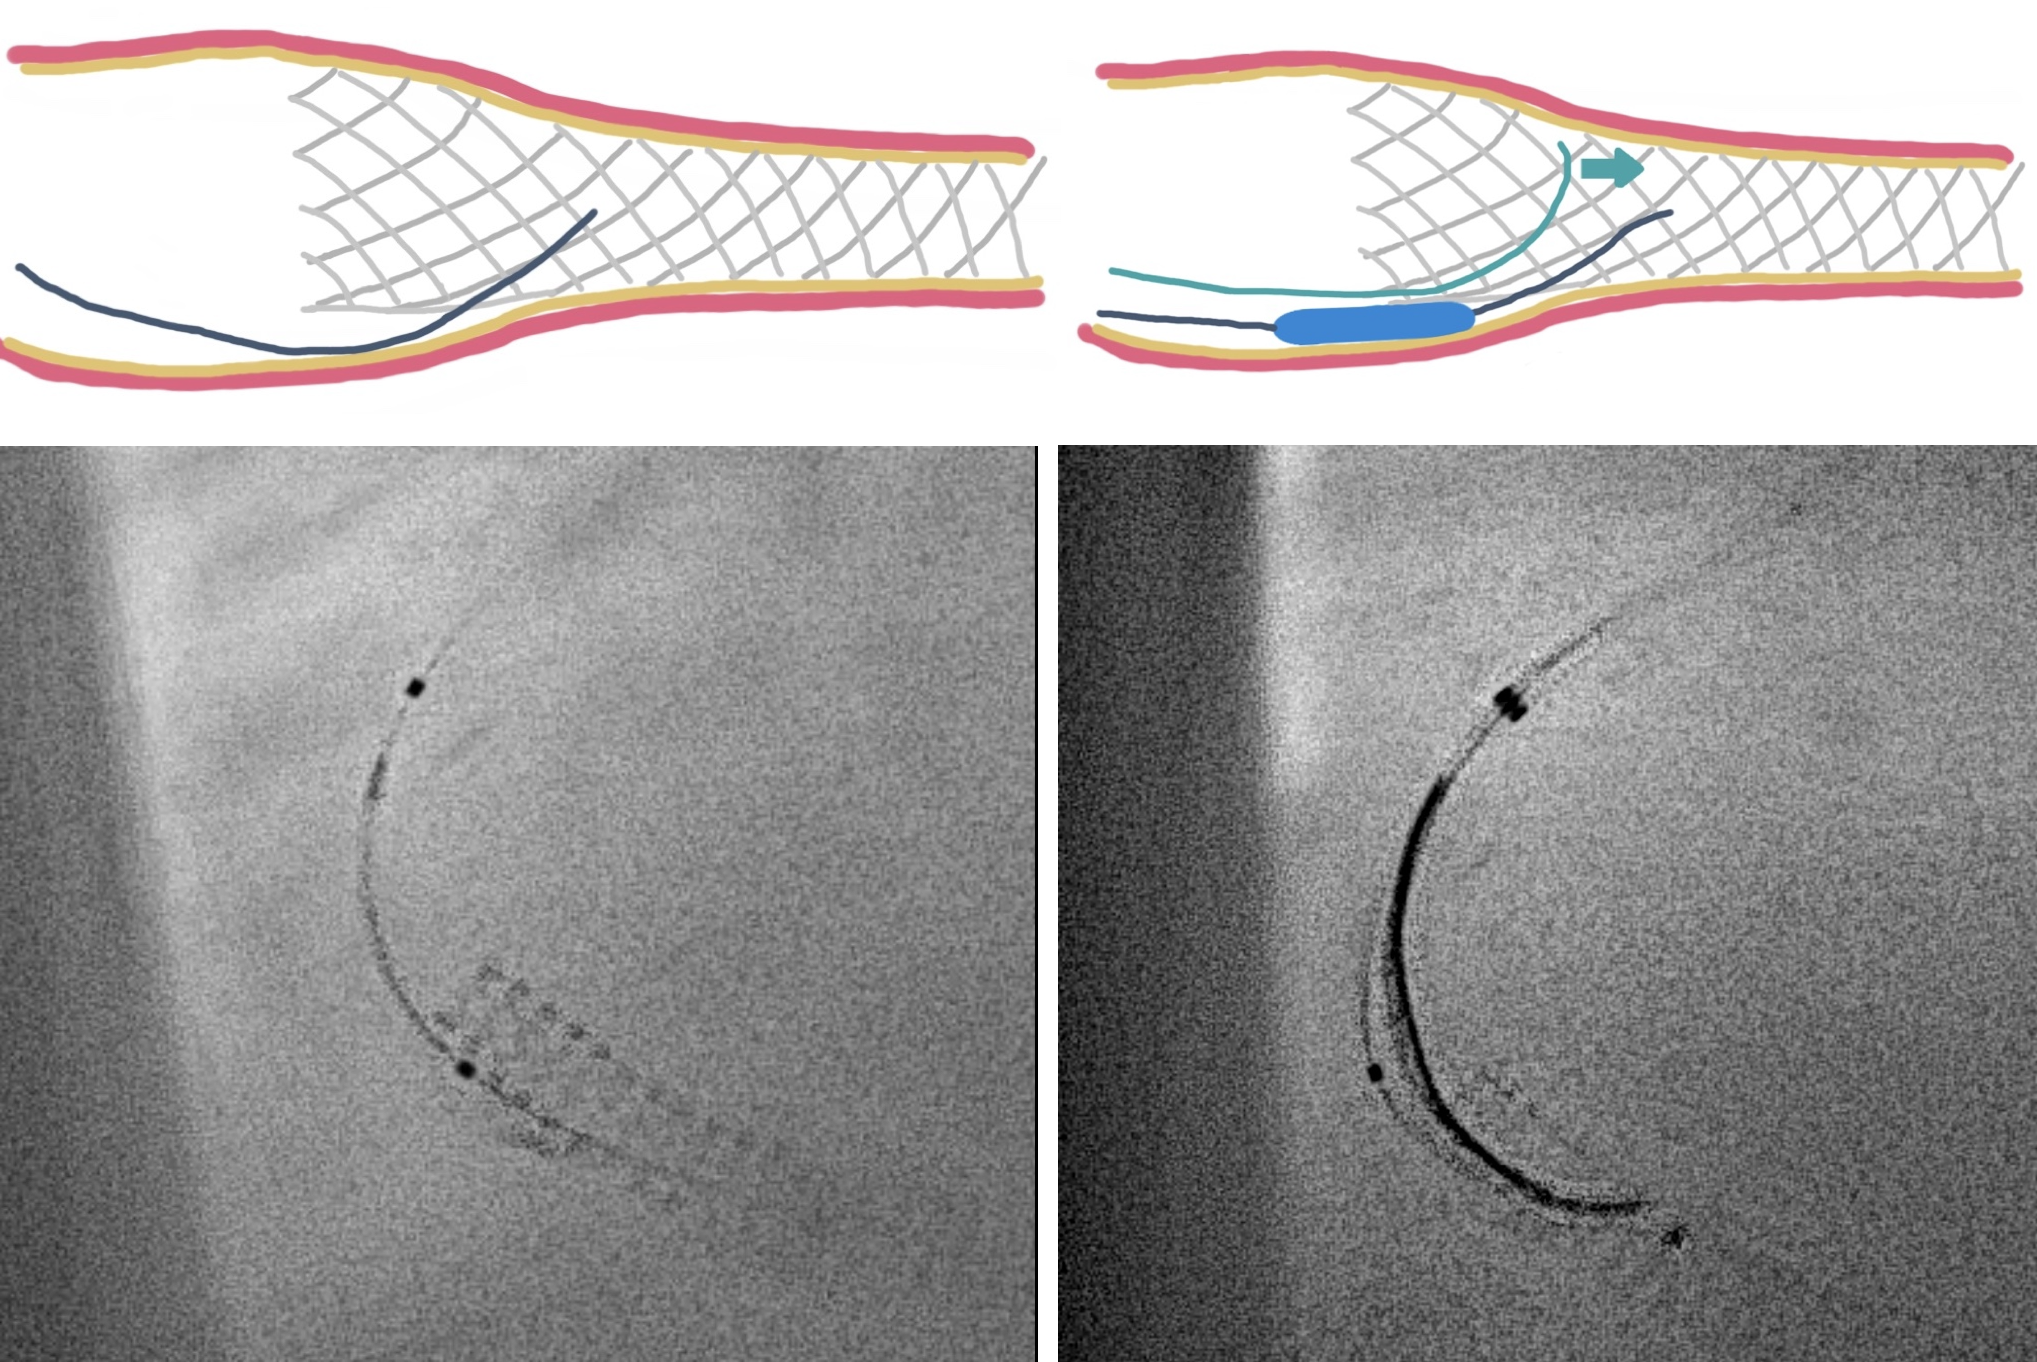

In anticipation of a high thrombus burden, intracoronary Tirofiban was given to mitigate thrombotic risks. The Terumo 6 Fr in 5 Glidesheath Slender was exchanged for a 7 Fr in 6 Glidesheath Slender to accommodate larger catheters while preserving radial artery access. Using a 7 Fr SAL 1.0 guiding catheter (Medtronic, USA), the Fielder FC 0.014” × 180 cm wire (ASAHI Intecc, Japan) was advanced to the distal RCA. Despite GuideLiner (Teleflex, USA) support, the Terumo Eliminate aspiration catheter could not advance beyond the mid-RCA. StentBoost imaging revealed the wire had wound along the aneurysmal vessel wall and passing through a previous stent’s strut. Attempts to reshape the wire tip for re-entry into the stent center were unsuccessful. Although stent crushing was considered, navigating the wire through the stent without damage was prioritized. An Euphora balloon (2.0 × 20 mm) was inflated at 2 atm to seal the gap between the stent and vessel wall, enabling the passage of a Runthrough NS Floppy wire into the distal RCA. IVUS confirmed the wire’s position within the stent, which remained intact. The wire was exchanged for an ASAHI Sion Blue Extra-support wire with a Caravel microcatheter. Thrombus aspiration was completed using the Eliminate catheter. Post-dilatation was performed with a Conqueror NC balloon (4.00 × 20 mm, APT Medical), followed by NC Emerge and Accuforce balloons (4.5-6.0 mm). IVUS confirmed excellent stent apposition, and TIMI 3 flow was achieved.

Case Summary

This case highlights the challenges of managing stents in STEMI patients with aneurysmal vessels. In such patients, vessel size is often underestimated during urgent procedures, leading to stent malapposition and an increased risk of thrombosis. IVUS or OCT is crucial for accurate vessel sizing and ensuring proper stent expansion. The gap between the stent and the vessel wall often causes the guidewire to preferentially pass through the aneurysmal vessel along the greater curve, rather than properly navigating through the stent. Finally, sealing these gaps with a small balloon facilitates guidewire passage and improves outcomes.